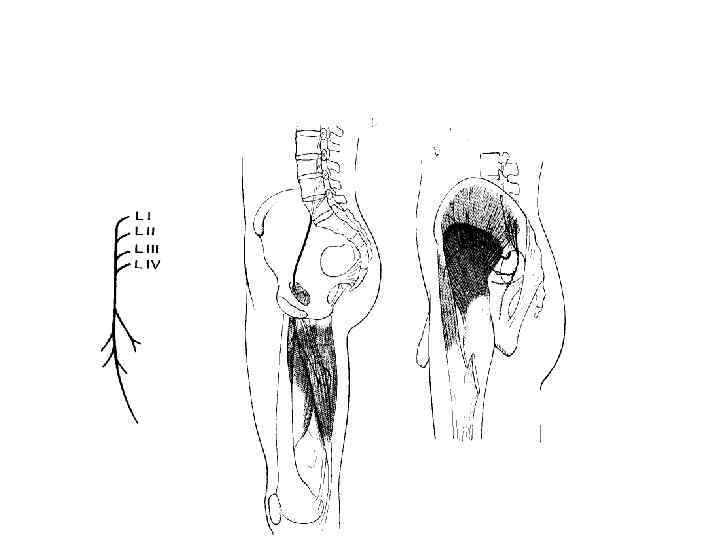

Поясничное сплетение

БЕДРЕННЫЙ НЕРВ, ИСТОЧНИКИ И ЗОНЫ ИННЕРВАЦИИ